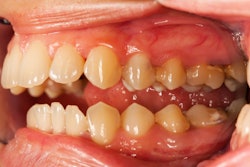

Selective serotonin reuptake inhibitors (SSRIs), commonly prescribed antidepressants, may slow gum regeneration by lowering protein levels that are important for bone development, according to a study recently published in the International Dental Journal.

The in vitro study isolated human PDLSCs from extracted premolars and exposed them to different concentrations of fluoxetine, an SSRI, during osteogenic induction. Fluoxetine was used as a model SSRI to examine its impact on PDLSC bone-forming ability and to explore underlying molecular mechanisms, they wrote.